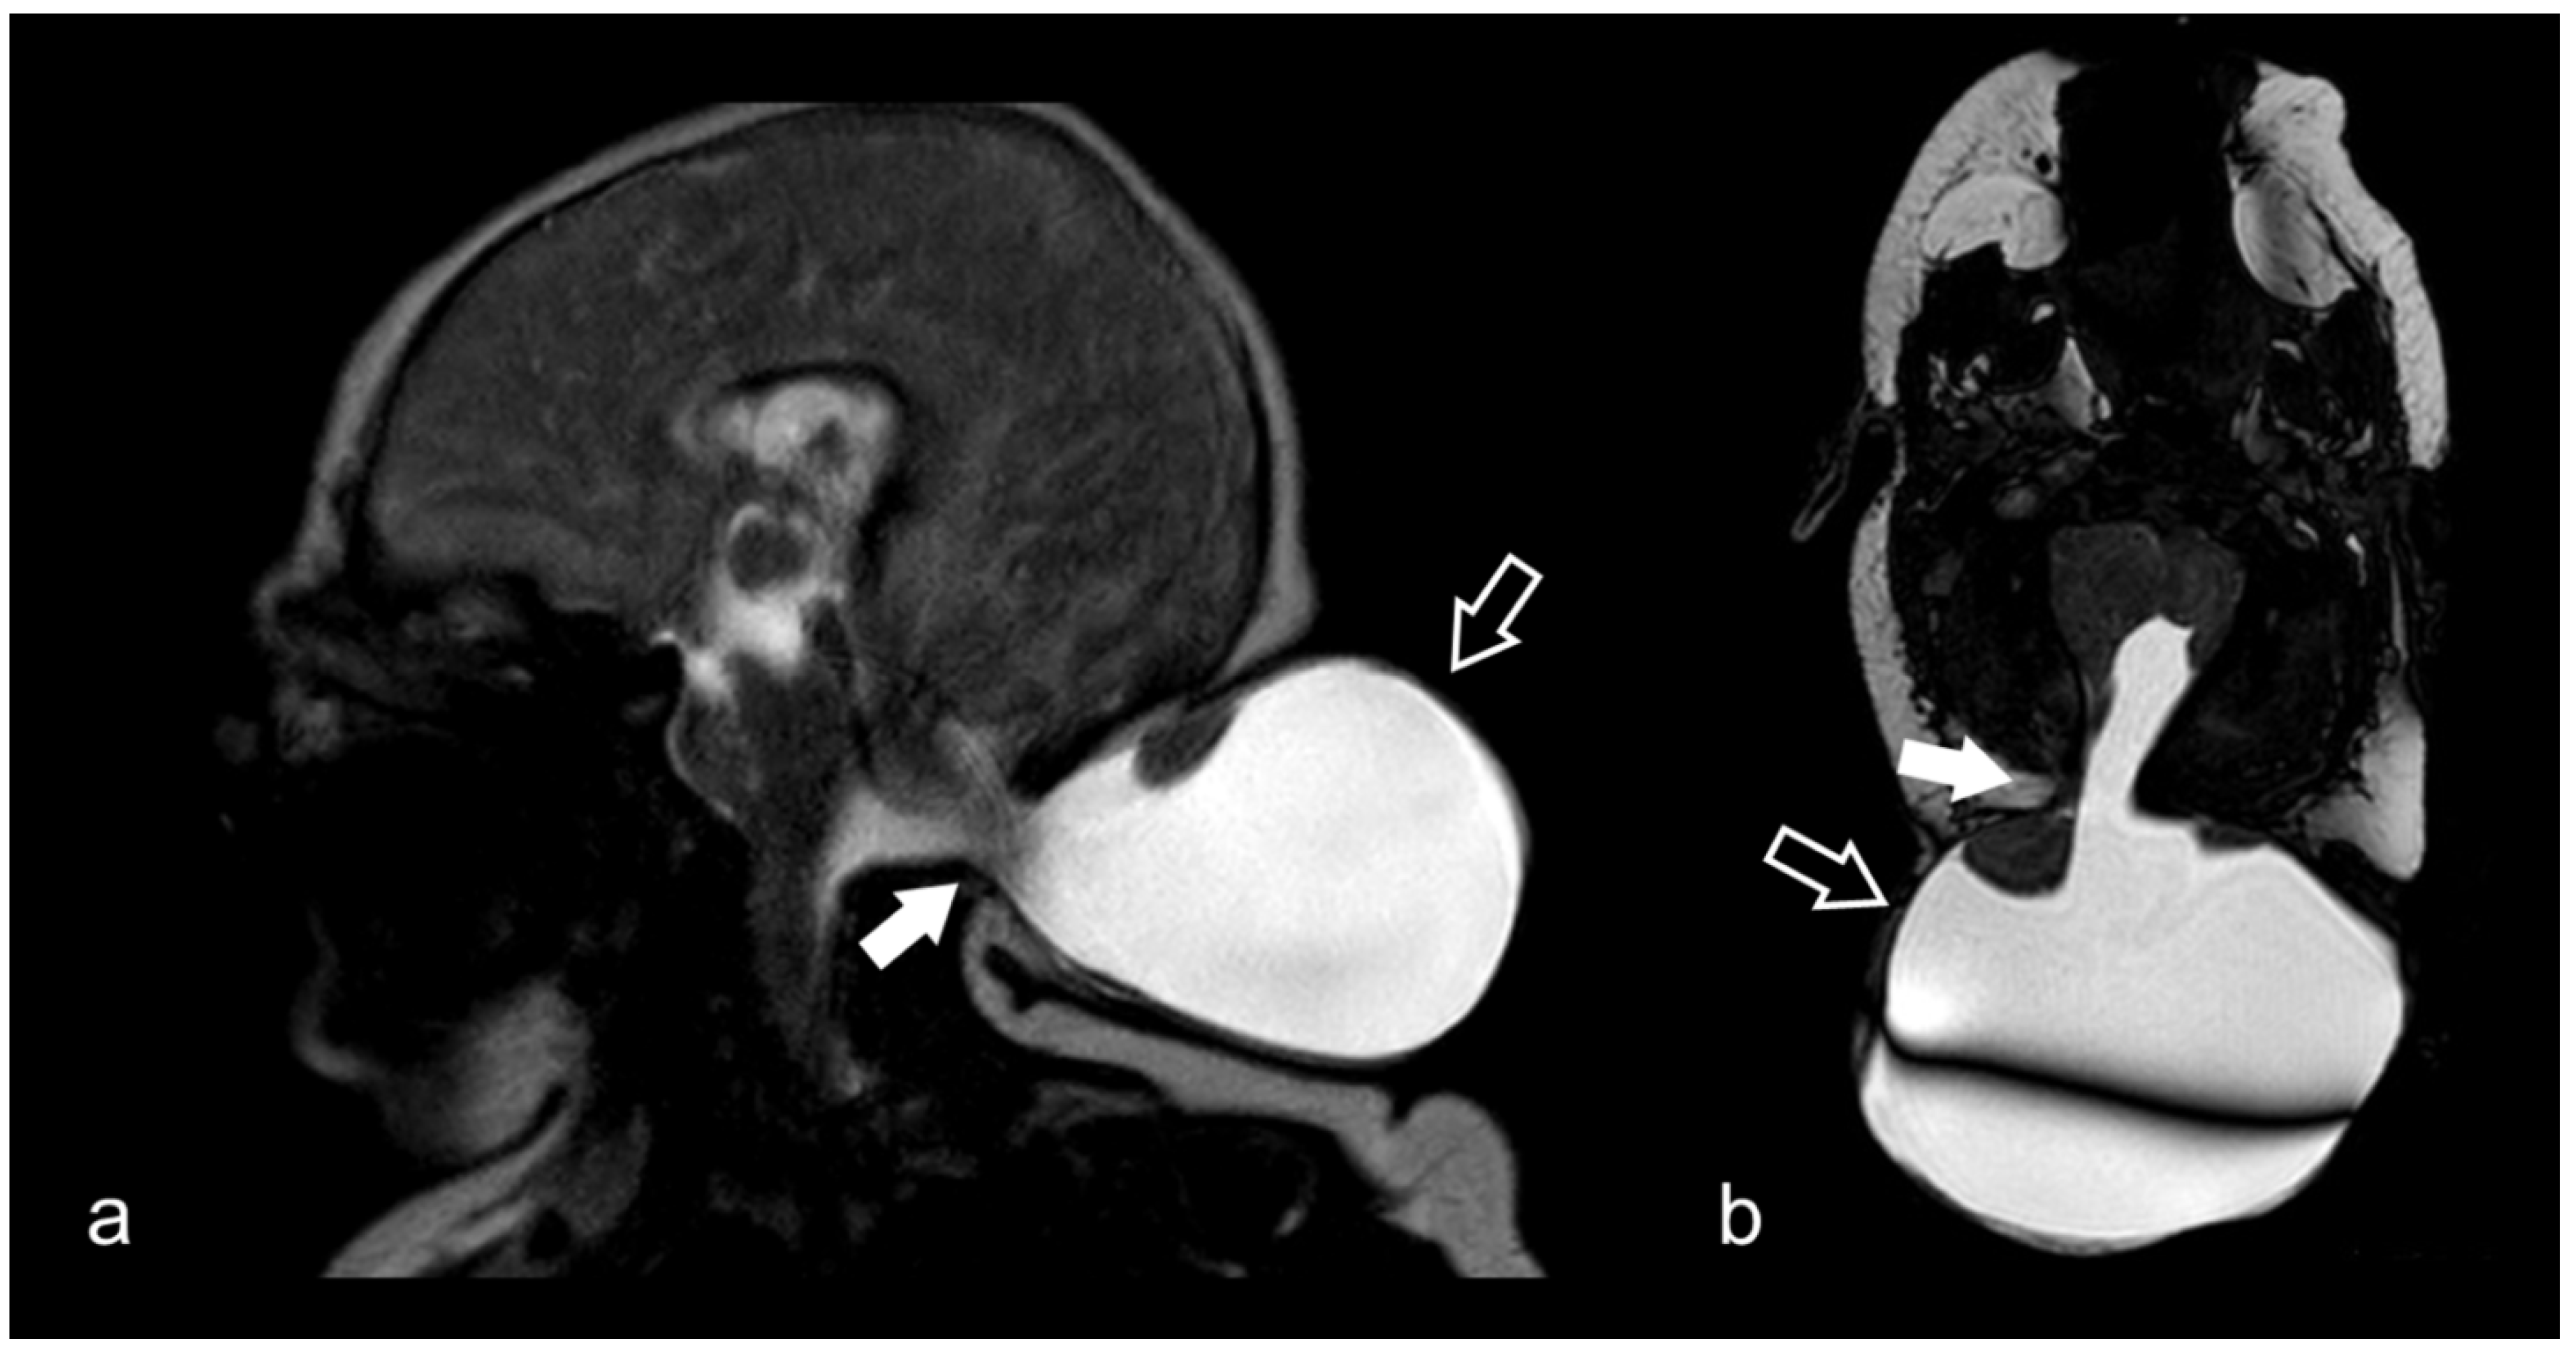

3.10. Cranio-Cervical Malformations (Chiari I)

- Dawes, B.H.; Lloyd, R.A.; Rogers, J.M.; Magnussen, J.S.; Bilston, L.E.; Stoodley, M.A. Cerebellar Tissue Strain in Chiari Malformation with Headache. World Neurosurg. 2019, 130, e74–e81. [Google Scholar] [CrossRef] [PubMed]